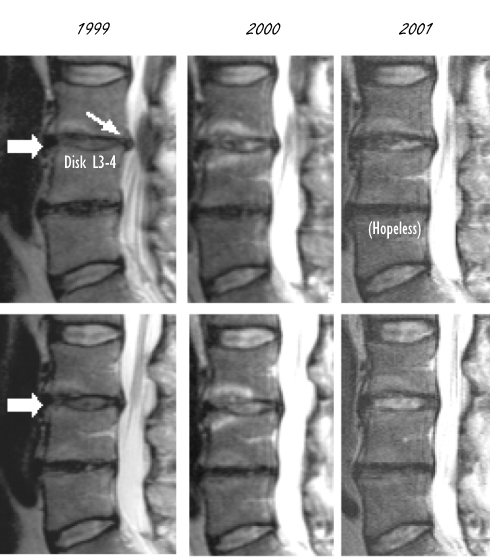

Op het moment dat de suppletieperiode begint, een jaar later en nog eens een jaar later, maken de onderzoekers een MRI-scan van de onderrug van de man.

De scans lieten zien dat gedurende de twee jaar dat de man glucosamine en chondroïtine slikte, de beschadigde tussenwervelschijf [bij de grote pijl] herstelde. De hoeveelheid kraakbeen in de schijf nam toe.

De man had ook een uitstulping aan de beschadigde tussenwervel [kleine pijl]. Die uitstulping drukte op de zenuwbaan in de wervelkolom, en veroorzaakte mogelijk de pijn en tinteling in de benen van de man. De uitstulping verdween gedurende de suppletieperiode.

De scans laten ook een versleten tussenwervelschijf zien waarop het kraakbeen bijna volledig is verdwenen. In die tussenwervelschijf treedt geen verbetering op.